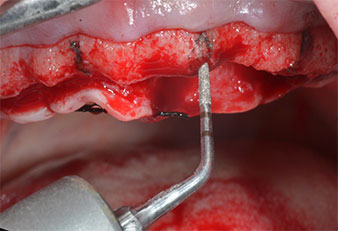

Para marcar las posiciones del implante y realizar la preparación piloto, se utilizó un inserto piezoeléctrico (Piezomed I1) con revestimiento de diamante y forma de llama (figura 3). Se tomaron precauciones para realizar movimientos hacia arriba y hacia abajo, con una potencia reducida, una irrigación completa y una baja presión (por debajo de 300 g). A continuación, se aplicó un inserto piloto (Piezomed I2A/I2P) para aumentar el diámetro inicial de 2 mm de los sitios de implante (figura 4), seguido de un inserto de 3 mm (Fig. 5).

En el caso que nos ocupa, no se utilizaron los insertos Z25P ni Z35P debido a la existencia de un hueso posterior relativamente blando, que se trató sin problemas con el I3A/I3P.